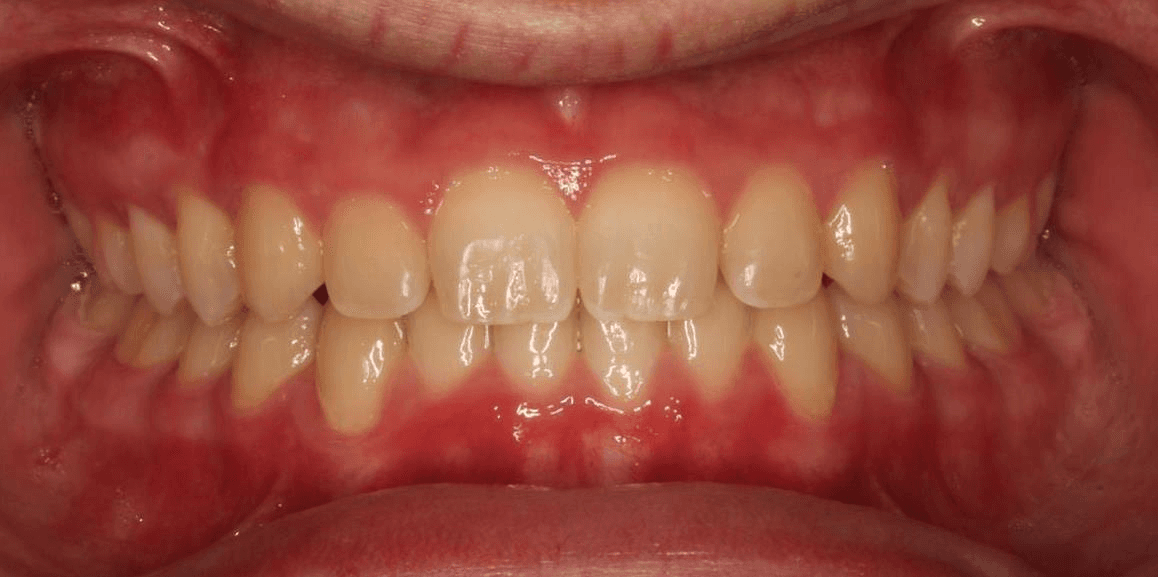

Final results

INTRAORAL